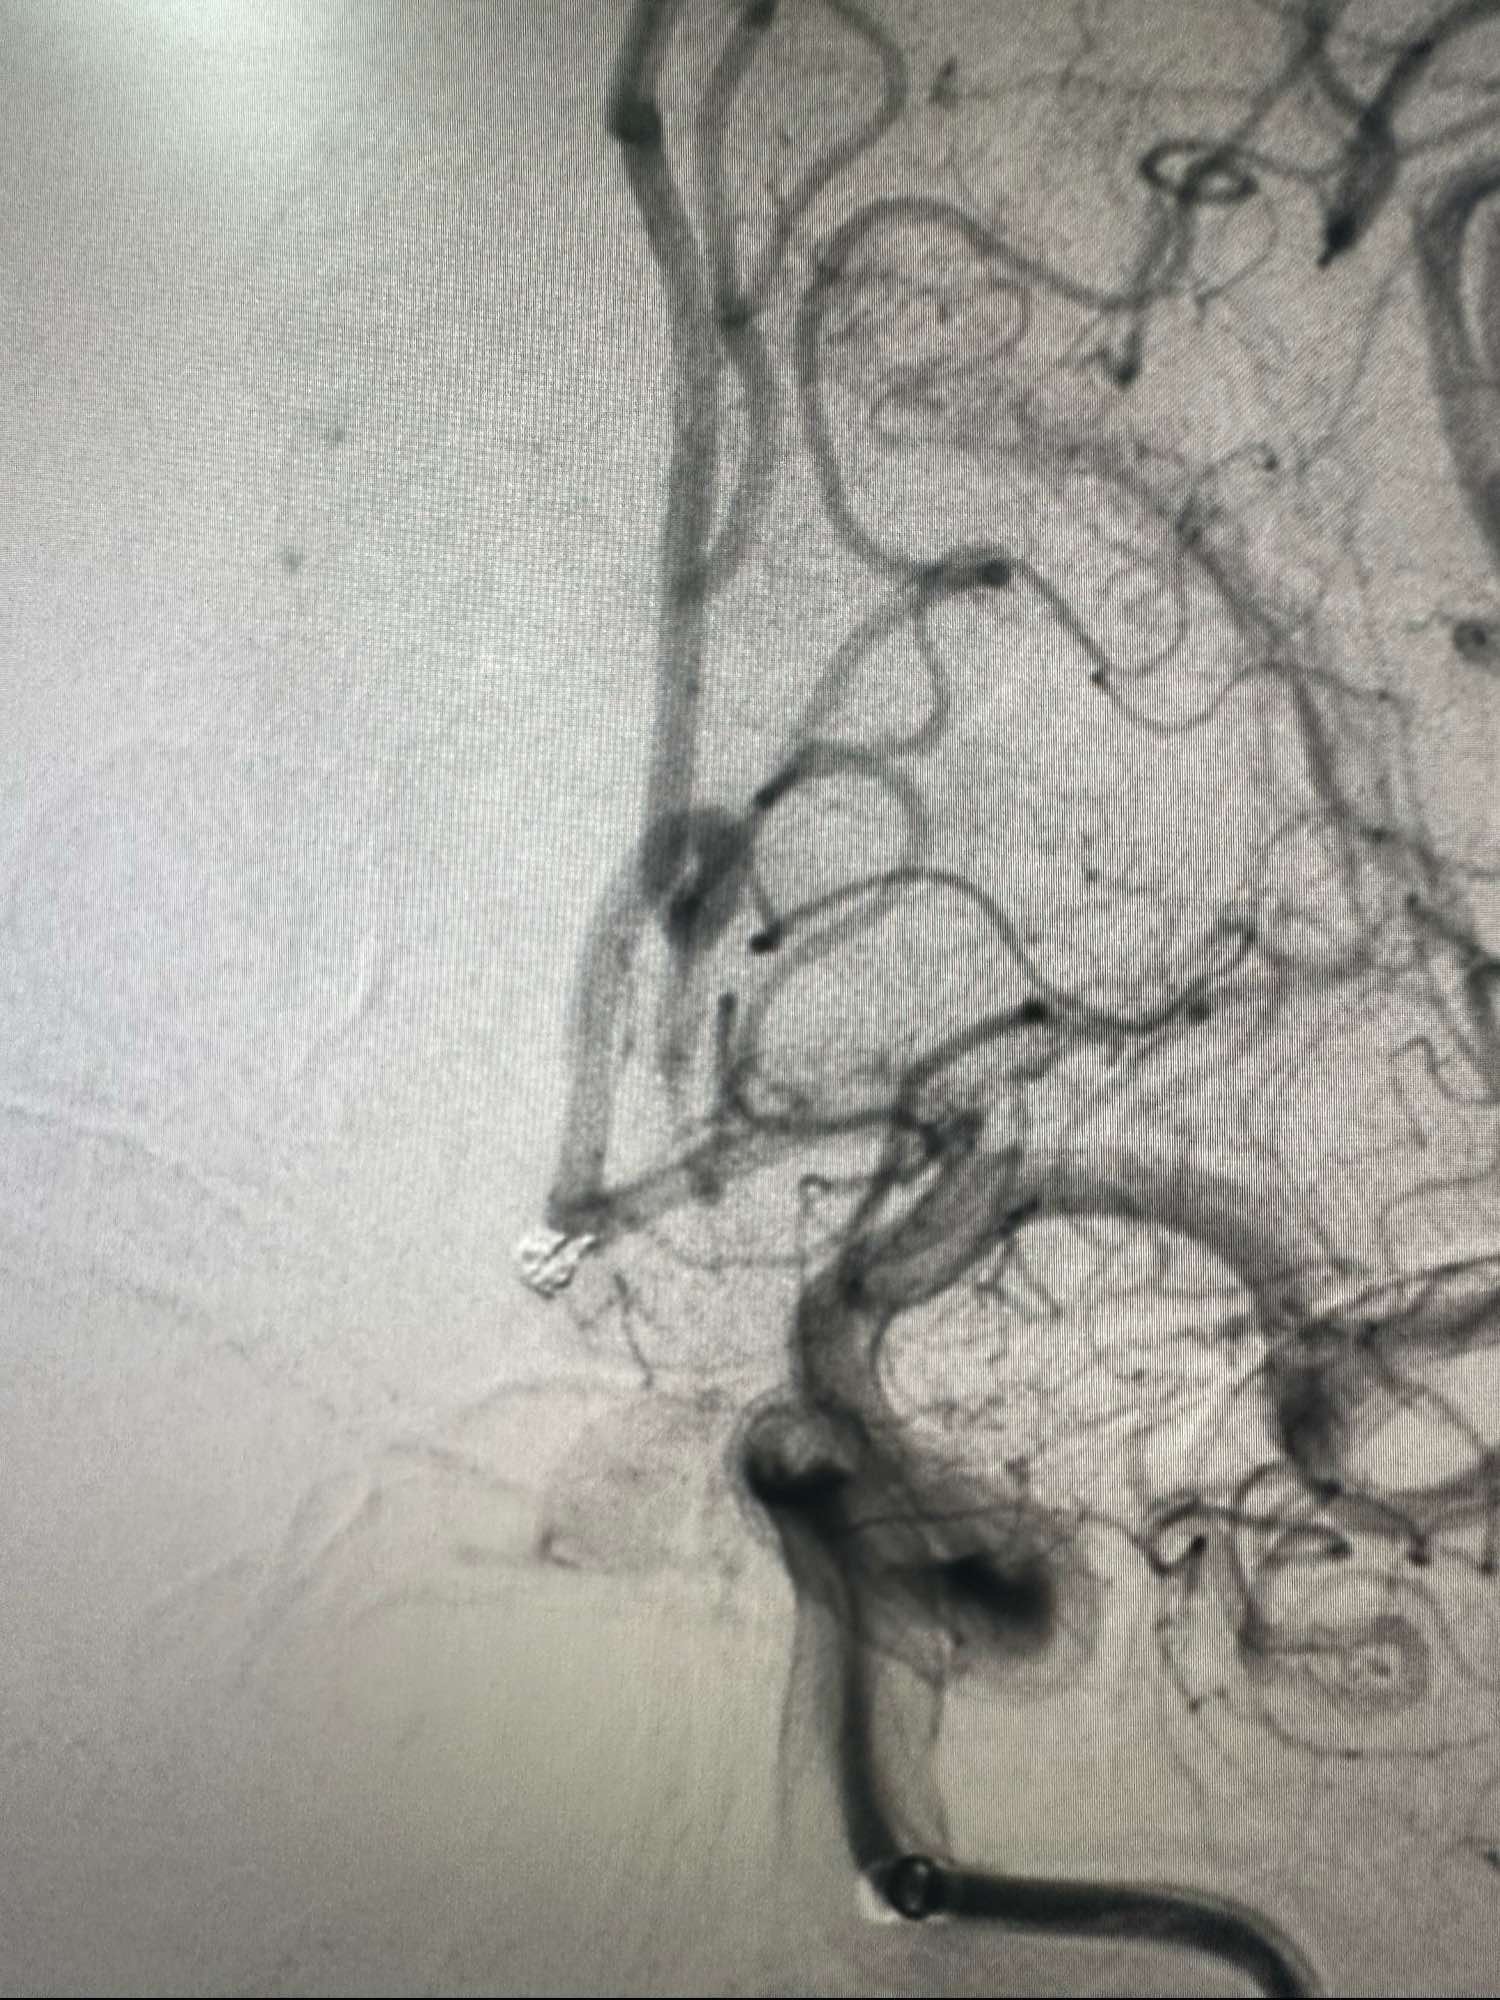

左侧颈内动脉路途,cook长鞘加上6F的银蛇中间导管

Sl_10的支架导管保护下。Enchon-10进入动脉瘤,一枚圈处理cosmos3D的圈2.5*4